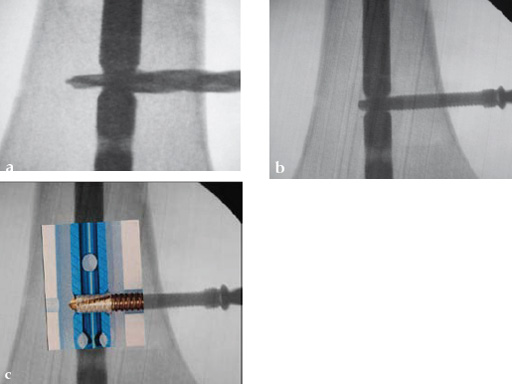

Drilling is identical but the near cortex needs additional reaming so it is wide enough to insert the sleeve. The enlarged hole at the near cortex will be filled by the thicker part which has a larger diameter than the rest of the screw (Fig 2). Use of the hand reamer has proven to be more tactile compared to drilling with machines (Fig 3). Power-driven drilling is only needed for very strong cortices, eg, the femur.

Drilling does not have to be very precise as the ASLS tolerates deviance. An exact amount cannot be given but up to 15 seems to be unproblematic (Fig 4).

The screw-sleeve construct is pushed into the nail's locking hole by hand. For the final placement, a light hammer (100 gr) may be used (Fig 8). You can actually feel and even hear the correct positioning. Use of a heavier hammer may lead to too deep placement or even pushing the sleeve too far through the locking hole. Control by image intensifier of the reamer and/or screw placement is only needed in the very early part of the learning curve (Fig 9).